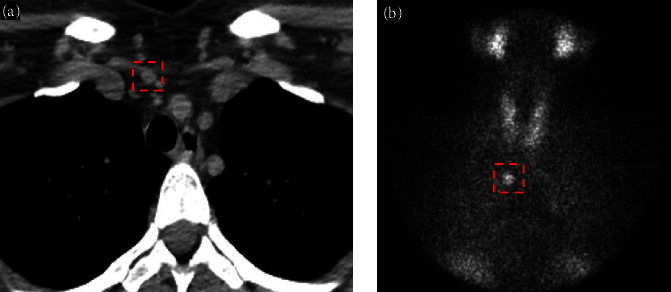

The higher risk for kidney stone in patients with primary hyperparathyroidism is well-documented; stone risk in patients with normocalcemic primary hyperparathyroidism (NPHPT) remains unclear. We present a case of recurrent calcium kidney stones in a patient with severe idiopathic hypercalciuria and NPHPT. The surgical resection of the parathyroid adenoma failed to reduce kidney stone risk (based on the 24-hr urine study) and kidney stone burden (based on ultrasound). This unique case examines the impact of surgical resection of an ectopic parathyroid adenoma on stone risk in a patient with NPHPT and recurrent calcium kidney stones.